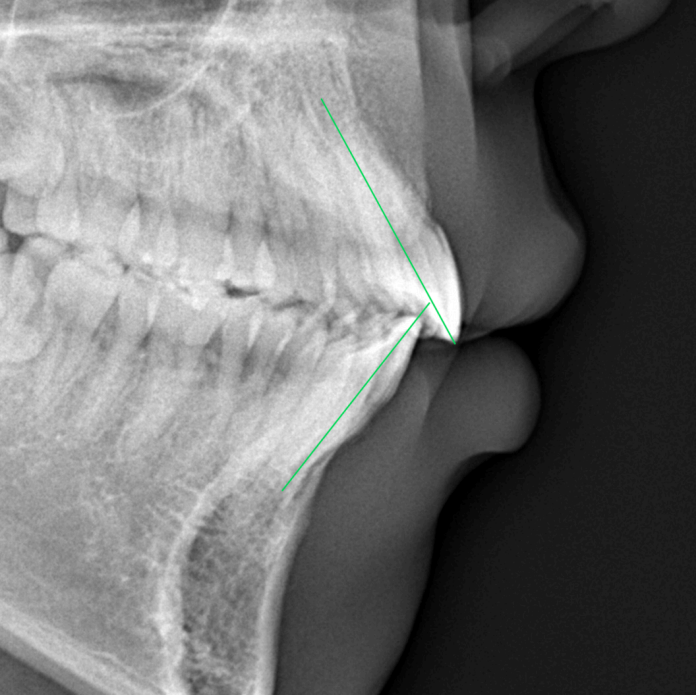

After

| 症例分類 | 上下顎前突 |

|---|---|

| 主訴 | 前歯が出ていて、口が閉じにくい |

| 年齢 | 20歳0ヶ月 |

| 性別 | 男性 |

| 抜歯部位 | 上下顎両側第一小臼歯 |

| 使用装置 | 歯の表側からのマルチブラケットによる矯正装置 |

| 治療期間 | 2年10ヶ月 |

| 保定装置 | 取り外し式保定装置 |

| 費用 | 相談料0円、検査料55,000円 動的矯正治療費935,000円 調整料6,600円×28回分 保定装置料0円 |

| リスク・注意点 | 上下の個々の歯の大きさに対して上下の顎が小さく歯が並ぶスペースが不足したために上下の前歯が前方に傾斜して、上下顎前突が生じています。これらを改善するために、上下顎両側第一小臼歯を抜歯して、このスペースを用いて歯を排列しました。歯の動き方には個人差があり、予想された治療期間が延長する可能性があります。 治療中は矯正歯科装置が歯の表面に付いており、歯が磨きにくくなるため、むし歯や歯周病が生じるリスクが高まります。ハミガキを適切に行ってお口の中を常に清潔に保ち、さらに、かかりつけ歯科医に定期的に受診することが大切です。 顎間ゴムの使用状況、定期的な通院など、矯正歯科治療には患者さんの協力が必要であり、それらが治療結果や治療期間に影響します。 治療の経過によっては当初予定していた治療計画を変更する可能性があります。 歯を動かすことにより歯根が吸収することがあります。 保定装置の装着時間が十分確保できない場合、歯並びや、咬み合せの「後戻り」が生じる可能性があります。 |